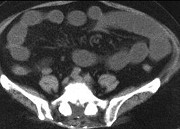

- 单项选择题男,30岁, 有胆结石病史,近日腹痛、腹胀, CT检查如图,应诊断为  (    )

- A、胆石症

- B、胆石性肠梗阻

- C、肠结核

- D、小肠克罗恩病

- E、小肠淋巴瘤